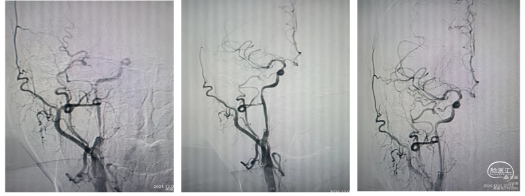

1、经桡动脉通路建设:局麻下置入右桡动脉7F薄壁桡动脉鞘。路图下在0.035in导丝及140cmsim造影导管配合下将7F远端通路导引导管在造影导管引导下到达右侧颈总动脉远端建立通路。下图1

2.置入保护装置:微导丝引入5mm保护伞,路图下将保护伞释放于该侧颈动脉岩骨段近端。下图2、3

3.球囊预扩张:

沿保护伞的微导丝将4mm×30mm球囊置于狭窄段,路图下以工作压缓慢扩张,造影显示狭窄较前改善,退出球囊。

4、支架植入:

沿保护伞导丝置入9mm×40mm Wallstent

支架,下图1、2。支架跨越狭窄段开放良好,残余狭窄,下图3。沿保护伞的微导丝将4mm×30mm球囊置于狭窄段行后扩张一次,回收保护伞,下图4。

2、置入保护装置:微导丝携带2.0Ⅹ12mm冠脉球囊扩张狭窄部位,下图1。置入5.0mm保护伞于颈内动脉C1段狭窄以远,下图2。

4、植入支架:撤出球囊,沿保护伞导丝输送7一10一40mm自膨支架,铆定狭窄部位。固定支架推送杆不下移,缓慢释放支架。造影显示支架位置良好,沿保护伞导丝送入单弯造影导管回收保护伞于体外造影显示:支架位置良好,残余狭窄不明显。